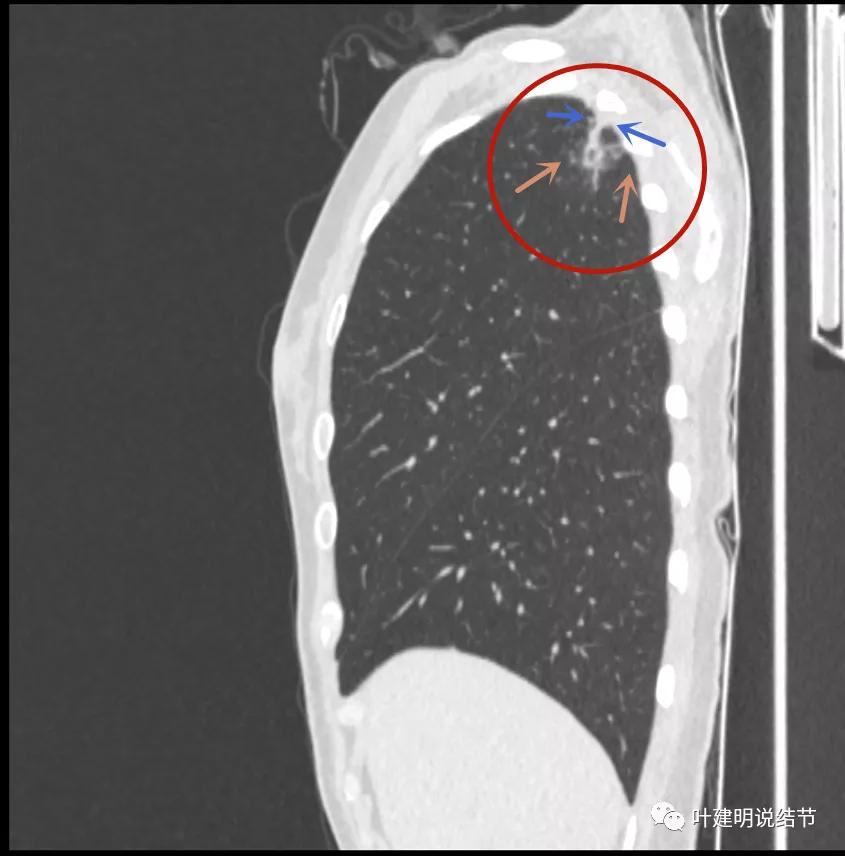

胸壁侧病灶较厚,模糊(蓝色箭头),仍见卫星灶(绿色箭头)

主病灶出现,粉色箭头示病灶密度较高,边上有磨玻璃影,甚淡(砖色箭头)

病灶有空洞(黄色箭头),主病灶边上见条索状高密度影(细红色箭头),邻近胸膜有粘连(蓝色箭头)